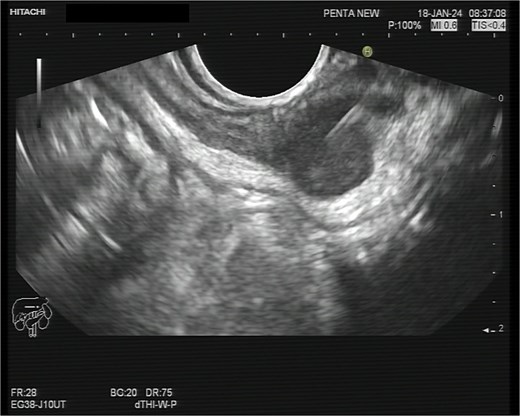

A 75-year-old woman with a past surgical history of serous papillary ovarian carcinoma underwent complete debulking surgery and adjuvant chemotherapy treatment 2 years prior to her current presentation. During follow-up, increased FDG uptake along with a 1.2-cm mass was seen on a PET-CT on the serosal surface of the recto-sigmoid junction (Fig. 1). An attempt was made to evaluate the lesion using trans-rectal sonography. Radial sonographic view showed a 12 mm, hypoechoic, well-defined lesion located at the serosal surface of the recto-sigmoid junction (Fig. 2). After reverting to a linear view, the lesion was sampled with fine-needle biopsy (Fig. 3) and whitish thick cores were retrieved (Fig. 4). The procedure was uneventful and no adverse events were noted. Pathology revealed fragments of high grade serous carcinoma of tubo-ovarian origin. Relying on the histological information gained from the biopsy, it was known that the lesion although not obvious to the eye during surgery, had to be found and resected. The surgical procedure was challenging with multiple adhesions, which made it difficult to locate the lesion. Based on the valuable preoperative knowledge, the patient was able to have a complete debulking of the tumor mass.

Radial sonographic view of the malignant lesion at the 2 o'clock position.